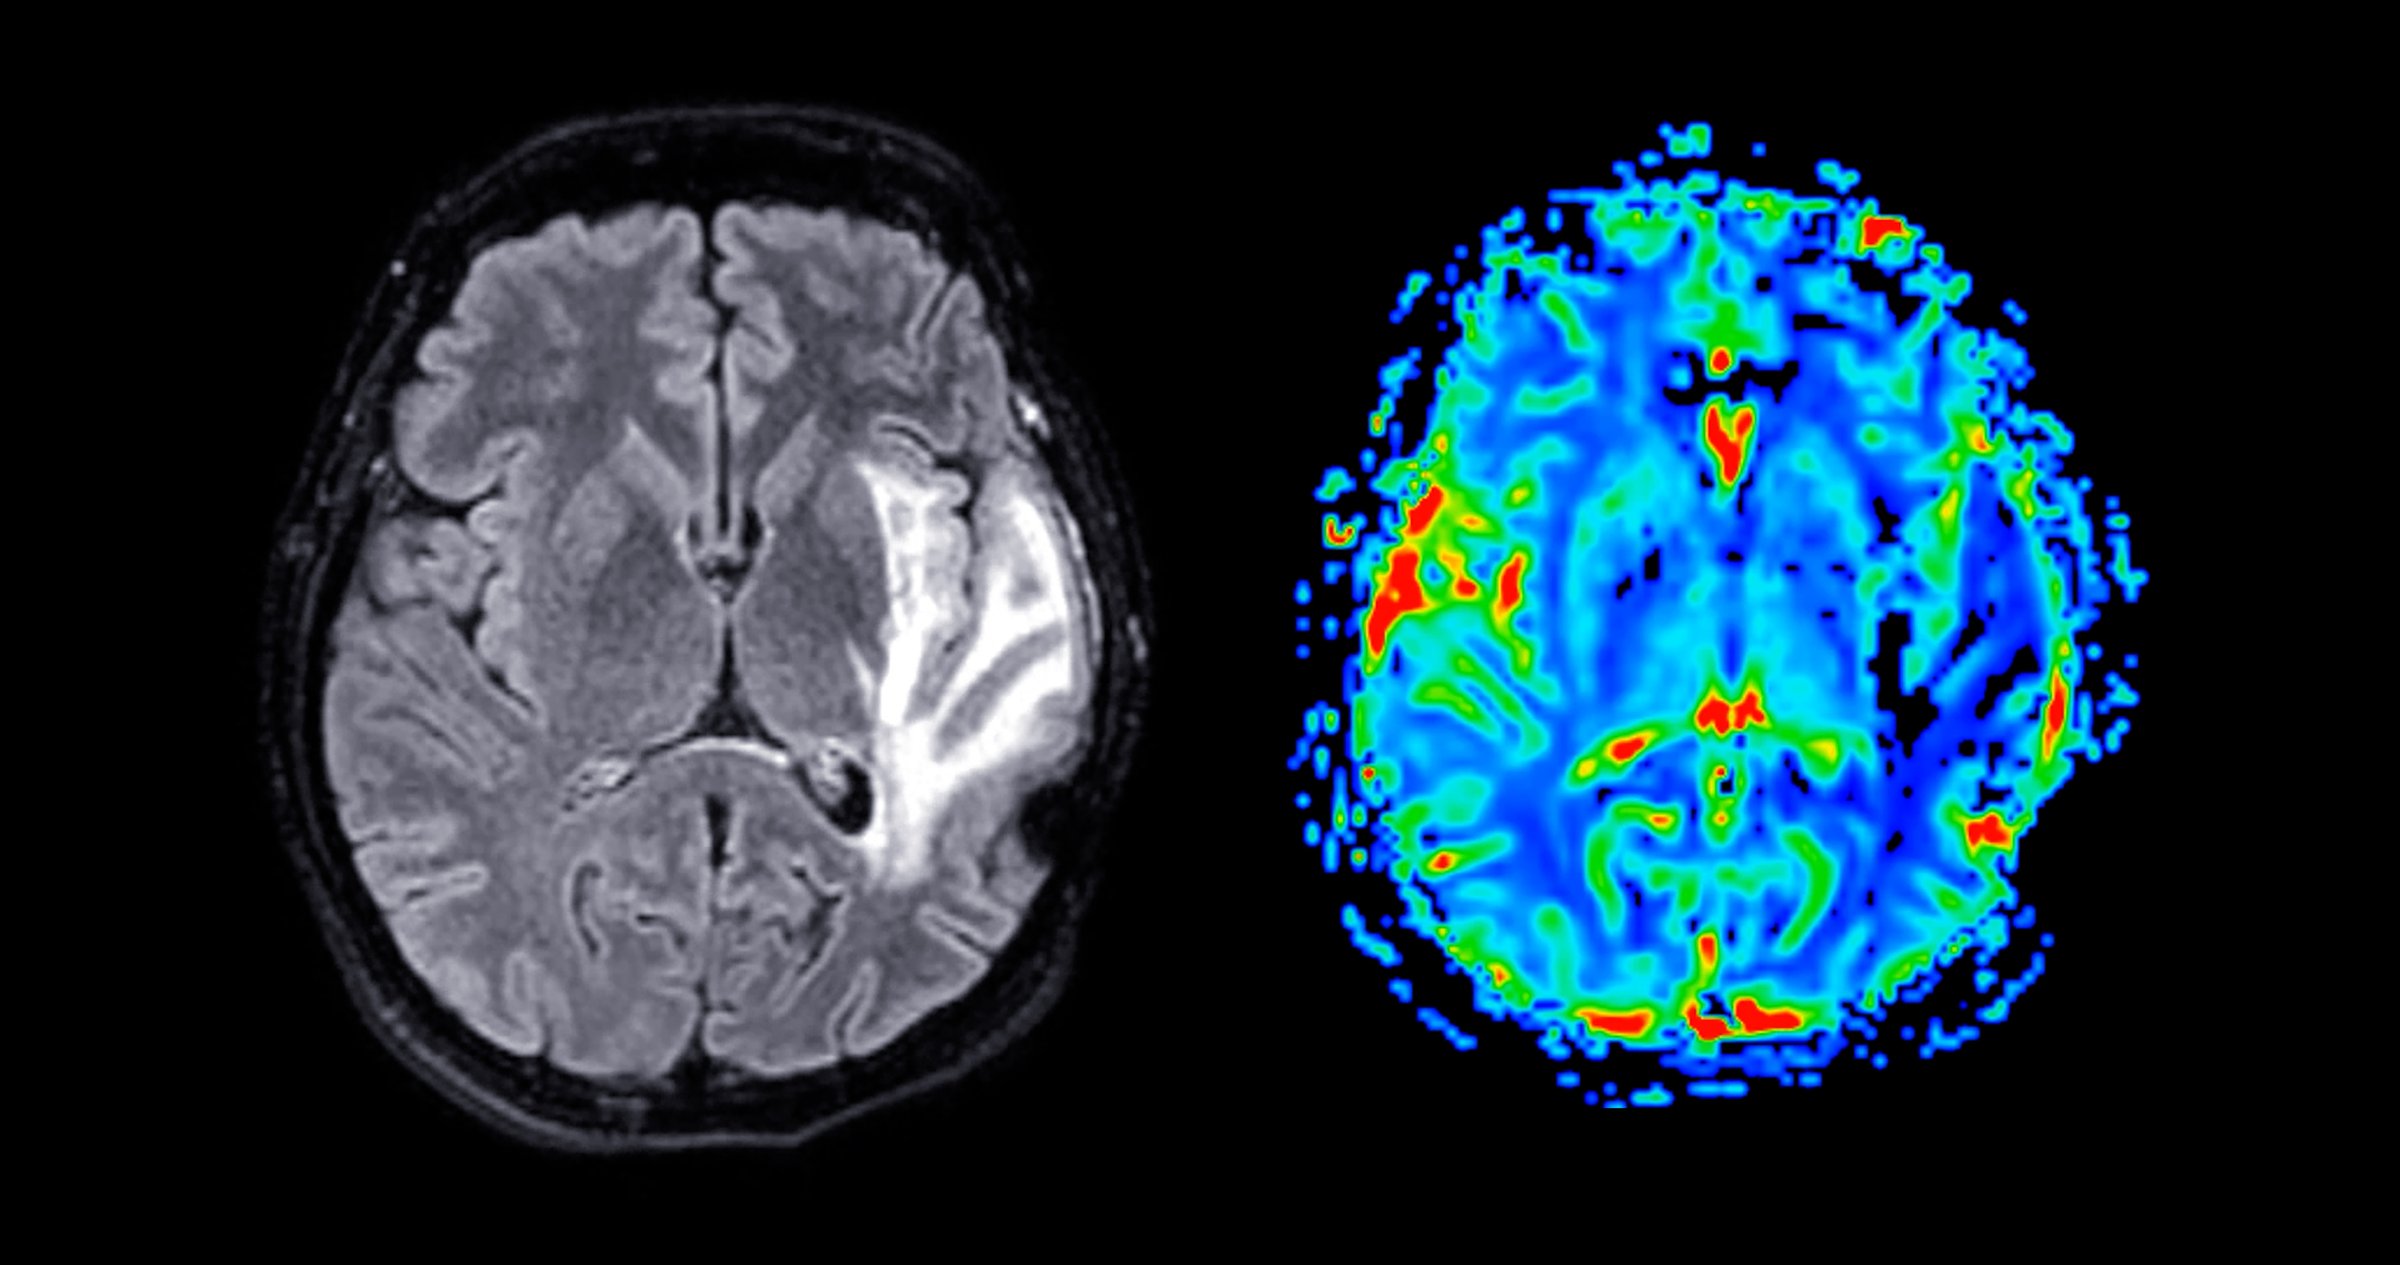

MRI brain perfusion imaging helps assess cerebral blood flow and tissue viability. It aids in diagnosing strokes, tumors, and other neurological conditions.

MRI & CT Imaging

Advanced brain and tissue imaging for detailed neurological assessments and early detection of conditions.